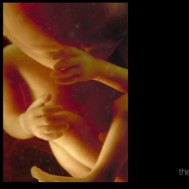

Gallery